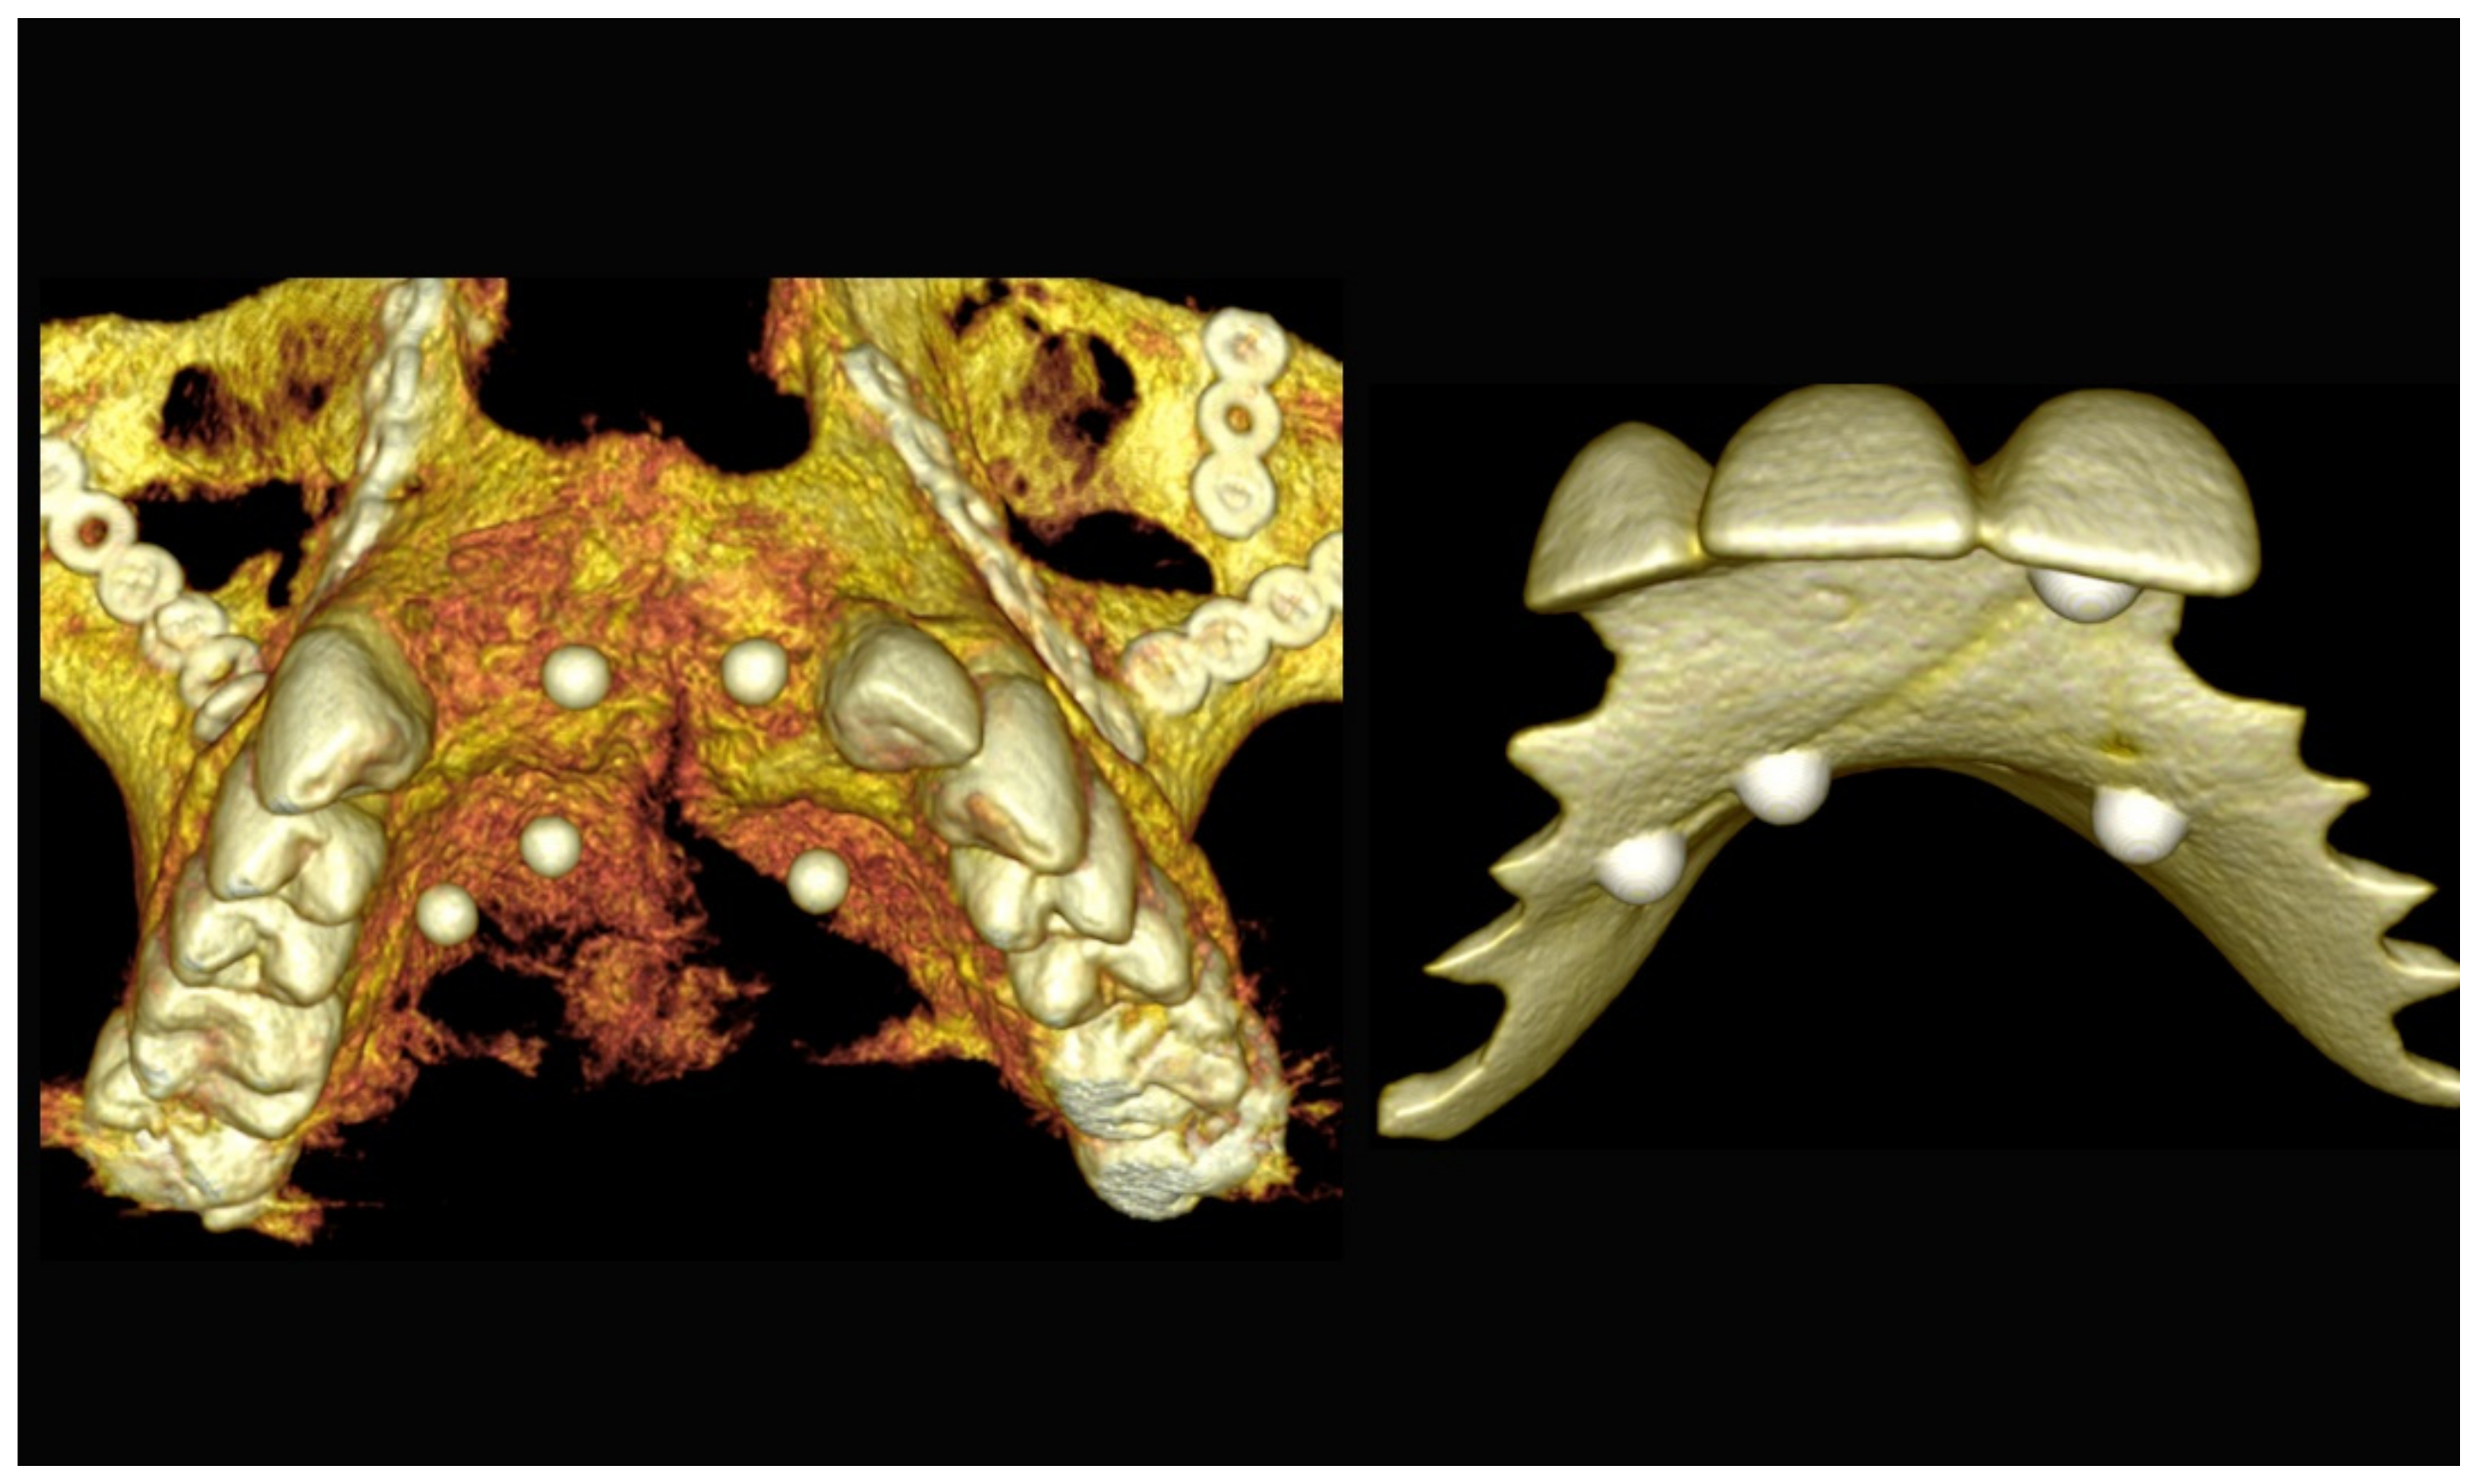

3.2. Step 2: CBCT Scan of the Patient and the Prosthesis with Integrated Reference Markers (Dual-Scan Technique)

6.2.2. Preoperative Documentation

6.2.3. Image Segmentation and Virtual Planning: